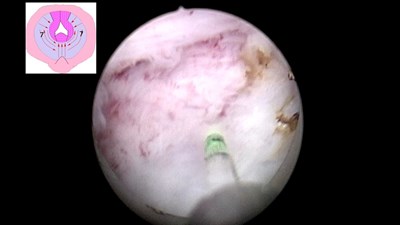

En bloc резекция стенки мочевого пузыря с опухолью с последующей инцизией предстательной железы

Операцию выполняет Сорокин Николай Иванович.